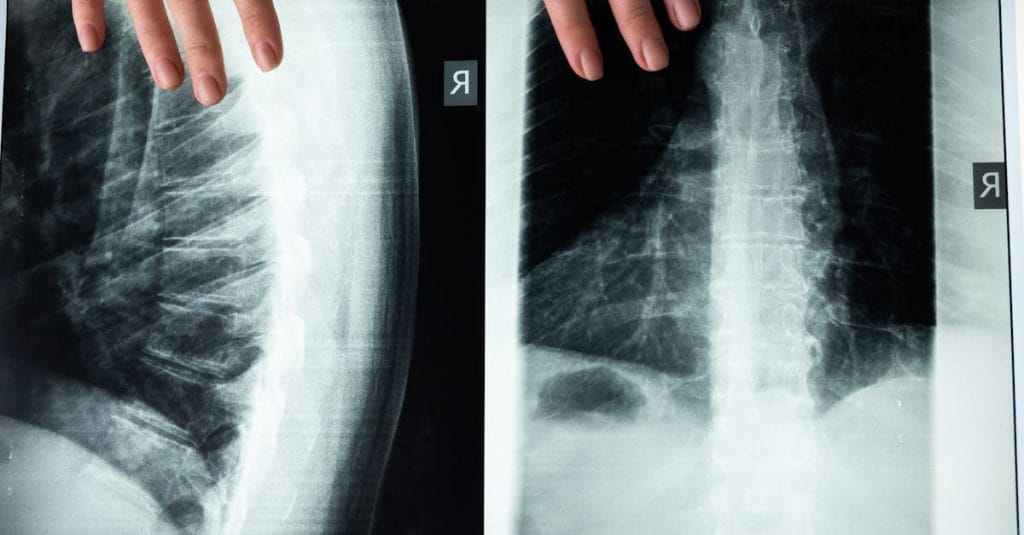

Expliquer le mécanisme de la décompression vertébrale

La décompression neurovertébrale agit en étirant doucement la colonne vertébrale, ce qui permet de créer un espace entre les vertèbres. Cette technique vise à réduire la pression sur les disques intervertébraux, ce qui est particulièrement bénéfique pour les personnes ayant des problèmes tels que les hernies discales, les bombements discaux ou d’autres pathologies vertébrales. En desserrant les tensions et en libérant les nerfs compressés, la décompression vertébrale aide à restaurer une fonction nerveuse optimale et à améliorer le flux sanguin dans la région de la colonne.

Un autre aspect vital de la décompression vertébrale est son impact sur l’équilibre général de la colonne. En corrigeant les désalignements, cette méthode contribue à restaurer l’alignement idéal des vertèbres, ce qui se traduit par une meilleure posture et une diminution des maux de tête et des douleurs cervicales. Un bon soutien de la colonne vertébrale est crucial, car il joue un rôle central dans l’équilibre musculaire et la prévention des douleurs à long terme.

Lorsqu’elle est pratiquée de manière adéquate, la décompression neurovertébrale peut favoriser un soulagement significatif des douleurs chroniques, telles que celles causées par des hernies discales ou des sciatique. Grâce à des appareils de traction spécialement conçus, cette méthode agit en étirant progressivement la colonne vertébrale, permettant ainsi de créer un espace entre les vertèbres. Cela favorise non seulement la circulation sanguine mais également la régénération des tissus et la réduction de l’inflammation, tous des facteurs clés pour retrouver un état de bien-être.

Un autre aspect fondamental de la décompression vertébrale est son impact positif sur l’équilibre musculo-squelettique. En soulageant les tensions accumulées sur la colonne vertébrale, cette approche favorise une meilleure posture et permet au corps de se stabiliser. Cela signifie également qu’il est possible de prévenir le développement de futurs problèmes, en préservant ainsi le confort de la colonne vertébrale dans le temps. Une posture améliorée contribue à une réduction du stress sur les articulations et aide à maintenir un poids santé, ce qui est essentiel pour une santé durable.